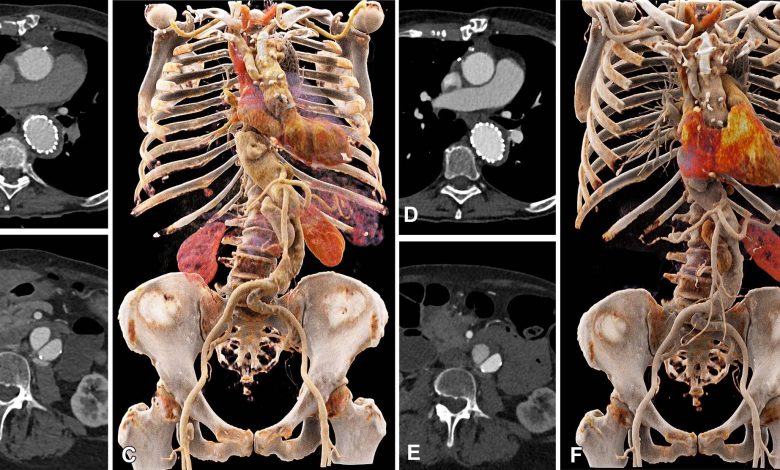

Comparação da qualidade da imagem entre EID CT com protocolo de meio de contraste padrão e PCD CT com protocolo de meio de contraste de baixo volume usando uma dose de radiação combinada. São mostradas imagens cinemáticas transversais e tridimensionais de CTA toracoabdominal em uma mulher de 71 anos no grupo 2. (A–C) Imagens de TC EID de terceira geração com seleção automatizada de tensão de tubo de 90 kVp. (D–F) Imagens de PCD CT com volume reduzido de meio de contraste de 52,5 mL e VMI a 50 keV. O intervalo de tempo entre os exames foi de 6 meses. CTA = angiografia por TC, EID = detector de integração de energia, PCD = detector de contagem de fótons, VMI = imagens monoenergéticas virtuais. Crédito: Radiologia: Imagem Cardiotorácica (2023). DOI: 10.1148/ryct.220140

A TC com detector de contagem de fótons reduz a quantidade de contraste necessária para a angiografia por TC (CTA), mantendo a qualidade da imagem, de acordo com um novo estudo publicado na Radiologia: Imagem Cardiotorácica.

A TC com contagem de fótons apresentou uma relação contraste-ruído mais alta, uma medida fundamental da qualidade da imagem, que se traduz em um protocolo de meio de contraste de baixo volume. O volume do meio de contraste foi reduzido em 25%.

Dois leitores independentes avaliaram a qualidade da imagem da TC com contagem de fótons como superior à da TC convencional em uma dose igual de radiação.

“Mostramos que a qualidade de imagem aprimorada da CTA com sistemas de TC com detector de contagem de fótons pode ser usada para reduzir a quantidade de meio de contraste administrado aos pacientes, sem reduzir o rendimento diagnóstico do exame”, disse o Dr. Alkadhi. “A qualidade da imagem manteve-se no mesmo nível dos exames anteriores de angiografia por TC nos mesmos pacientes usando uma TC convencional, apesar de termos reduzido o volume do meio de contraste.”